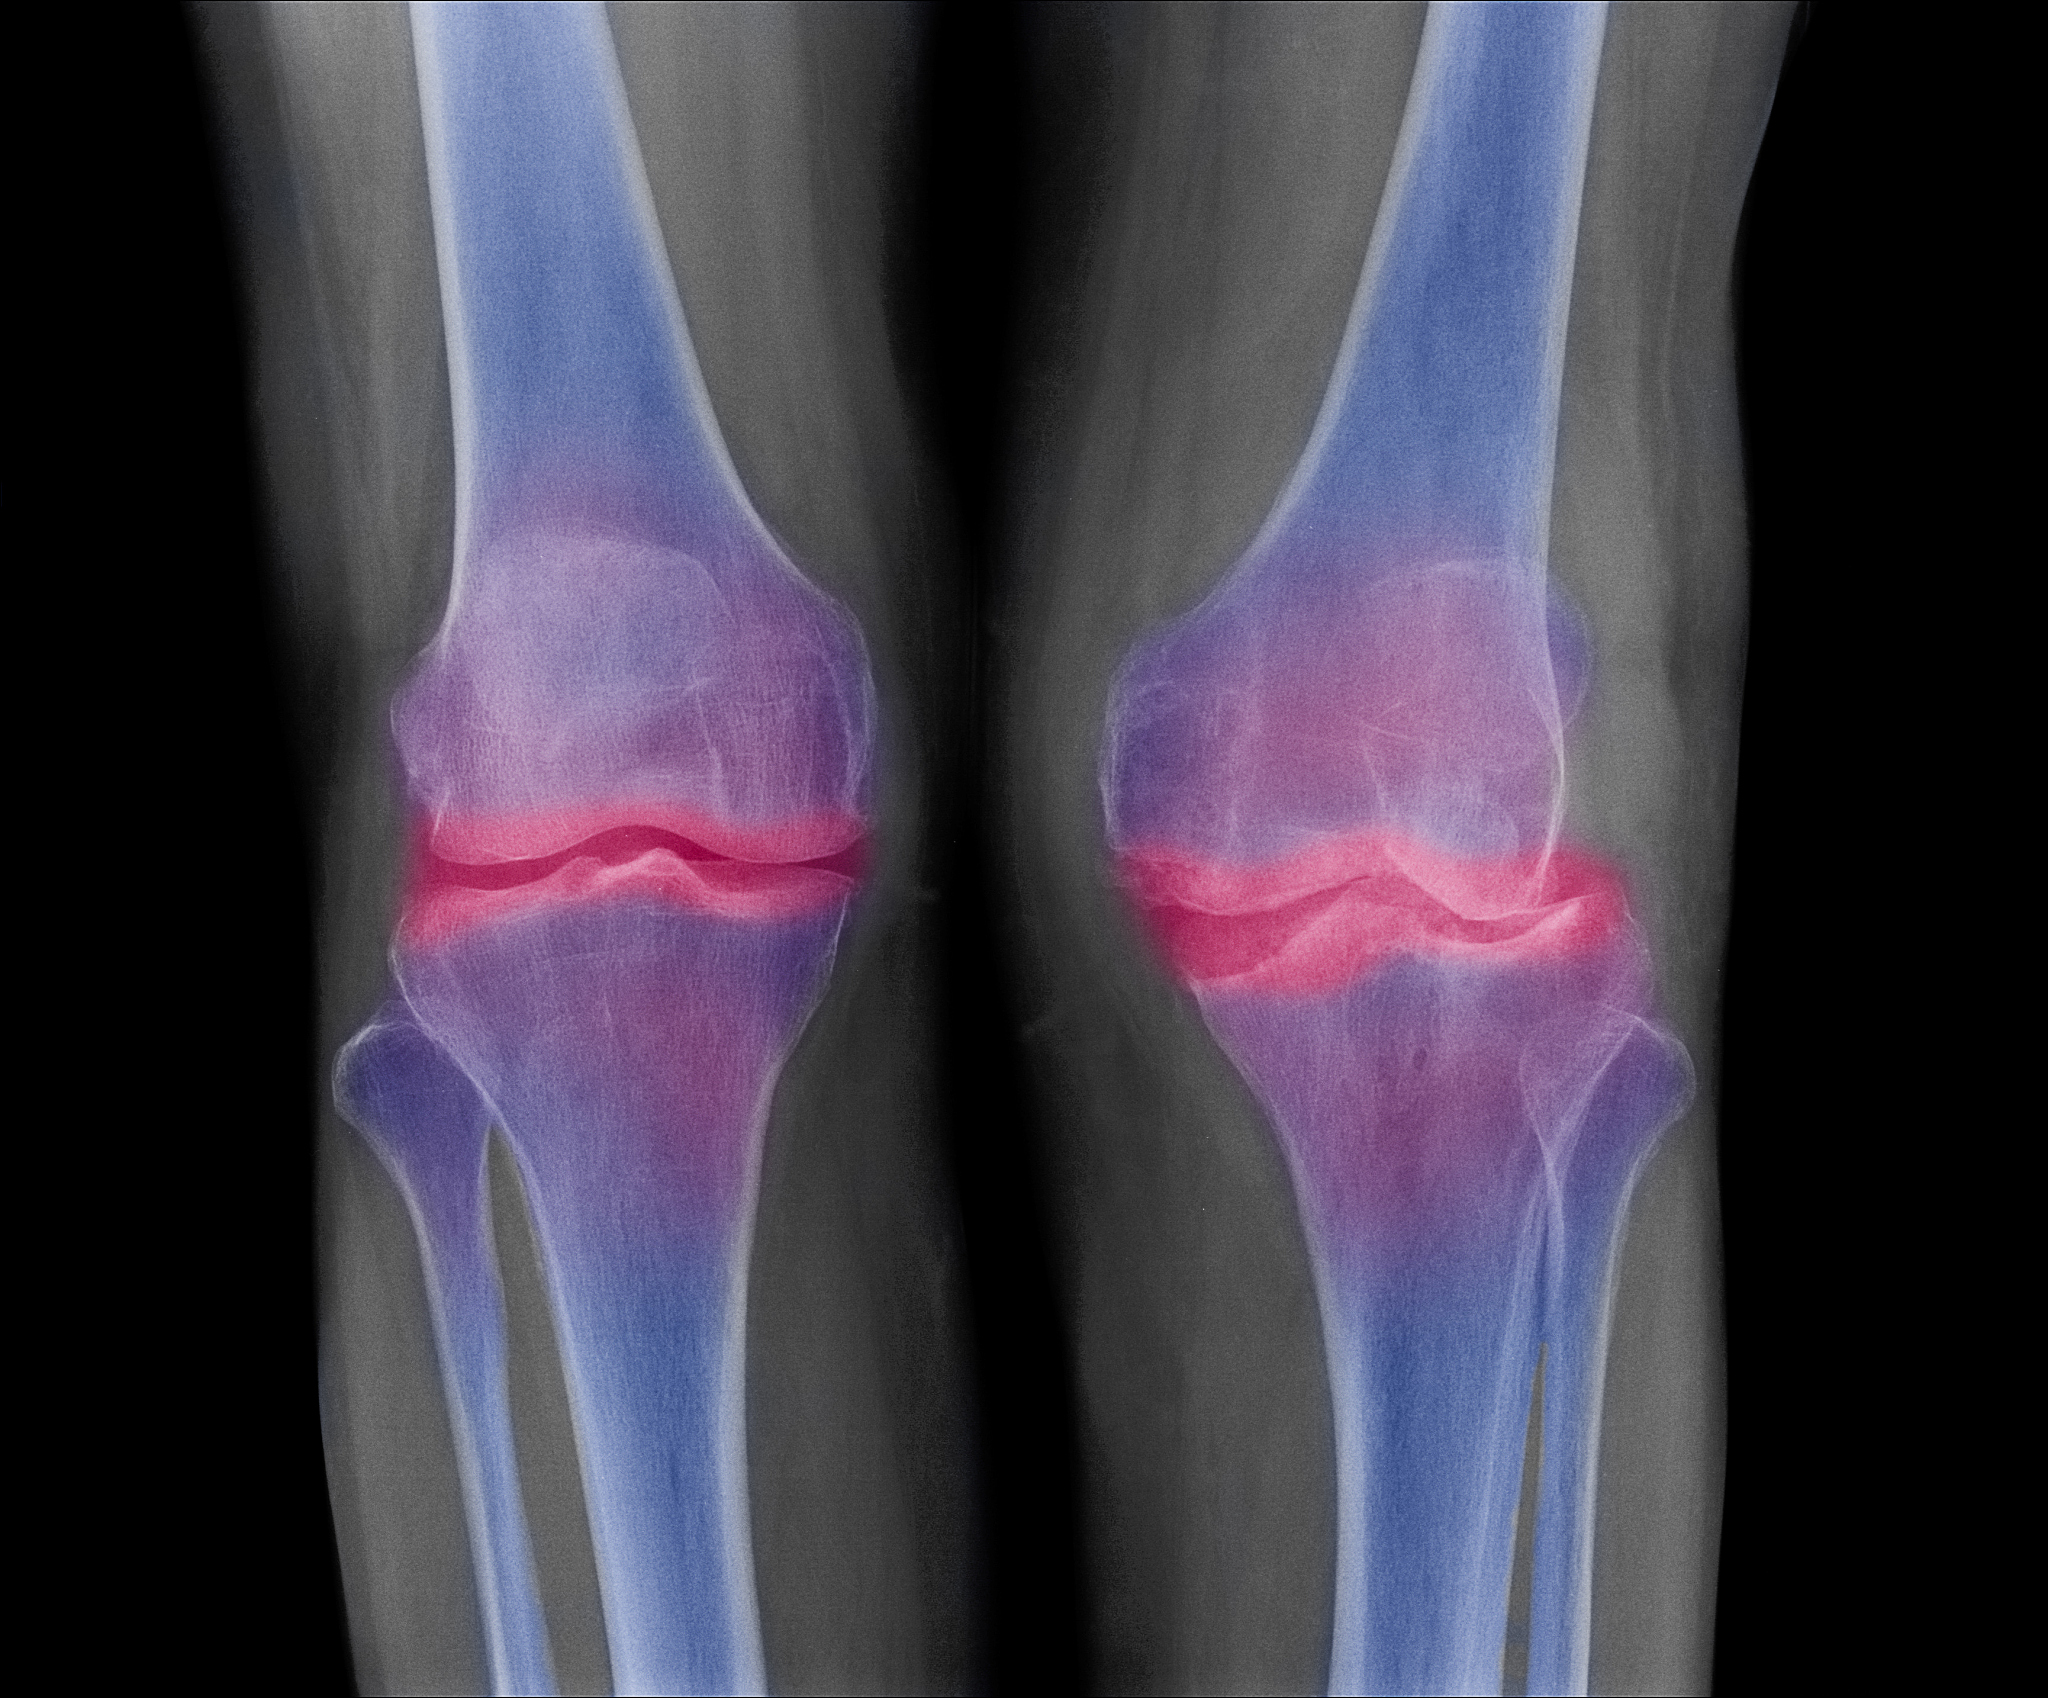

胫骨粗隆突出(也称为'胫骨结节突出')是指胫骨骨干前方突起的一块骨头,通常位于胫骨下三分之一的位置。这个突起通常是正常的解剖结构,不会引起任何症状或问题。

然而,有时胫骨粗隆突出可能会伴随其他症状,例如疼痛、肿胀、红肿、触痛等。这可能是由于外伤、骨折、骨质增生、骨骼畸形等原因引起的。在这种情况下,建议您咨询医生进行详细的评估和诊断,以确定是否需要进一步的治疗或管理措施。